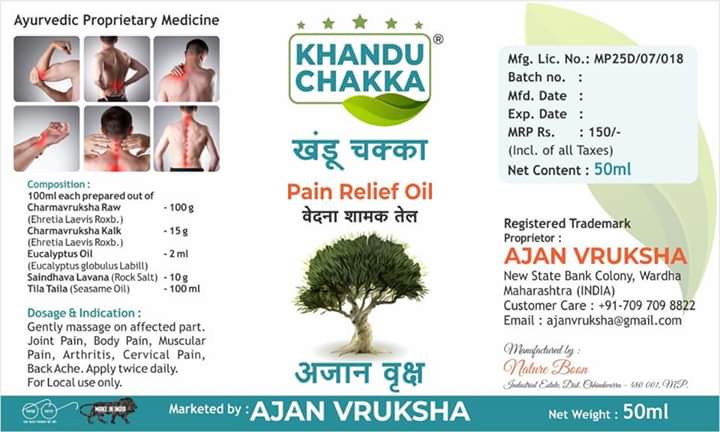

Khandu Chakka Herbal Pain Relief Oil

खंडू चक्का वेदना शामक तेल

Khandu Chakka Herbal Pain Relief oil for Joint Pain, Body Pain, Muscular Pain, Arthritis, Cervical Pain & Back Ache

"खंडू चक्का आणि अजान वृक्ष आयुर्वेदिक वेदना शामक तेल "

मिळवा वेदनांच्या त्रासापासून मोक्ष, वापरून अजान वृक्ष दुखण्यावर इलाज पक्का, खंडू चक्का खंडू चक्का

वेदना सहन करू नका त्यांचा विनाष करा सांधे दुखी, कंबर दुखी, व अष्या अनेक वेदनांवर आम्ही घेऊन आलो एकच उपचार

अधिक माहितीसाठी त्वरीत संपर्क करा 9923089064/7097098822